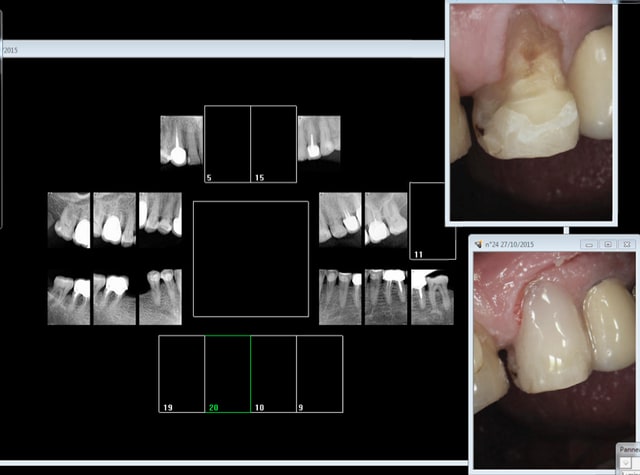

Capture d e cran 2015 10 27 17.41 - Eugenol